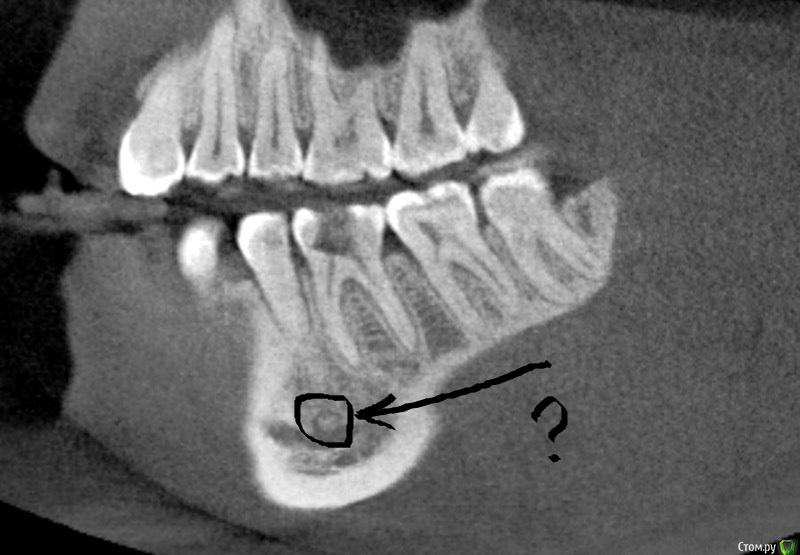

Рентгеновские снимки посттравматического остеомиелита челюсти: Медицинские случаи

Раздел: Образы вокруг